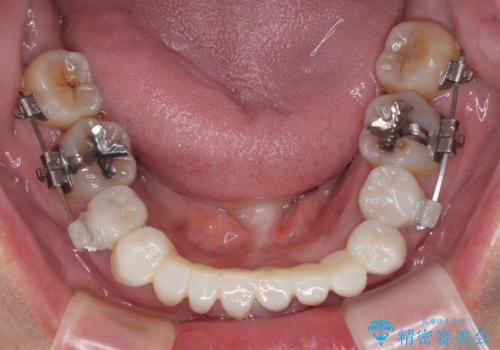

- 常に外れている下顎のブリッジと、前歯のデコボコと色を気にして来院された患者様です。

前歯のデコボコおよび奥歯の咬み合わせを改善するために、上顎左右の小臼歯を欠損スペースを利用して歯列を整え、矯正治療後に気になる上下前歯などをオールセラミッククラウンで美しく仕上げていくこととしました。

色や歯列が整ったことはもちろん満足いただけましたが、上顎の舌側転位していた前歯が綺麗に整ったことで違和感が減ったことを非常に喜んでいらっしゃいました。